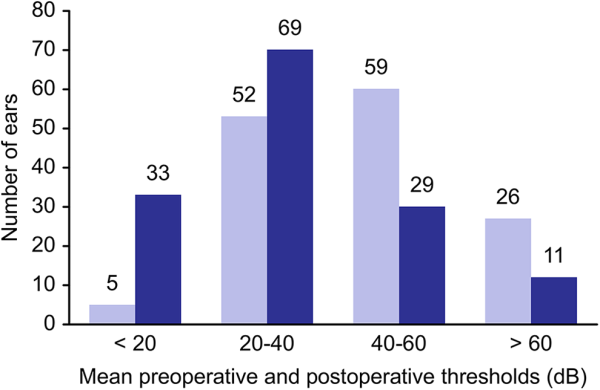

Comparison of the pre- and postoperative mean AC threshold showed that the hearing was worse in 12 (8.6%) ears, unchanged in 24 (17%) ears, and improved in 106 (74.4%) ears (Figure 3).

Figure 3

Hearing results after fat graft myringoplasty. Improvement in mean AC threshold.

In 33 (23.2%) ears, we obtained a final mean AC threshold of <20 dB; in 69 (48.9%) ears, we obtained a mean AC threshold between 20 and 40 dB; in 29 (20.4%) ears, we obtained a mean AC threshold between 40 and 60 dB; and finally in 11 (7.7%) ears, we obtained a mean AC threshold of >60 dB.

Preoperative mean BC threshold was 29.1 dB (5-70 dB) and did not change after surgery. Mean AC threshold was preoperatively 59.3 dB (17-95 dB) and significantly improved after surgery into 35.6 dB (10-85 dB; P < .0004). Preoperative ABG was 30.2 dB (5-70 dB) and also significantly improved into10.2 dB (5-65 dB; P < .0001; Table 2). We found no significant difference between the location of the perforation and the extent of hearing improvement (χ2 = 27.465, P = .283).

The mean preoperative ABG was 30.2 dB (5-70 dB), with 46.9% of ears at 20 to 40 dB and 9% of ears <20 dB. The mean postoperative ABG was 10.2 dB (5-65 dB), with 41.4% of ears at 20 to 40 dB and 51.7% of ears <20 dB. The ABG worsened in 5 (3.5%) ears, did not change in 32 (22.5%) ears, and improved in 105 (74.5%) ears.